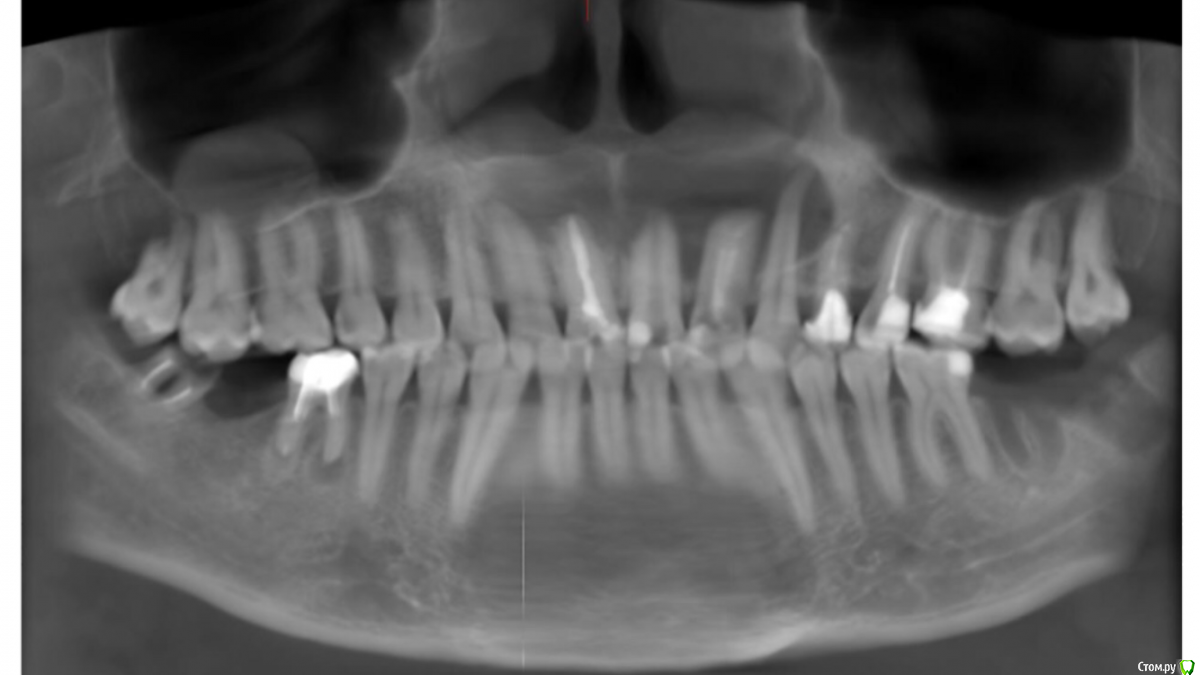

Гарриевич Опубликовано 13 декабря, 2016 Поделиться Опубликовано 13 декабря, 2016 (изменено) Просто для понимания и для других пациентов, которые может буду читать вашу тему. Вот тут "киста" размером в 2-3 см и это НЕ показание к удалению. Сейчас пациент проходит терапевтическое лечение, все симптомы исчезли. Размер поражения абсолютно не влияет на исход лечения Изменено 13 декабря, 2016 пользователем Гарриевич 5 Ссылка на комментарий

Сашуля Опубликовано 13 декабря, 2016 Автор Поделиться Опубликовано 13 декабря, 2016 Просто для понимания и для других пациентов, которые может буду читать вашу тему. Вот тут "киста" размером в 2-3 см и это НЕ показание к удалению. Сейчас пациент проходит терапевтическое лечение, все симптомы исчезли. Размер поражения абсолютно не влияет на исход леченияIMG_9649.PNGЗначит, возможно, мой зуб можно было спасти?!!!!Жаль, что не смогла попасть к Вам на приём. Все стоматологи разные, для кого-то это просто бизнес((( думаешь, идёшь к специалисту ..... Ссылка на комментарий